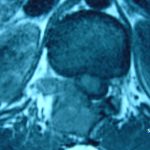

Εικ. 3: Μαγνητική τομογραφία α-στ Οβελιαία (Saggital) λήψη ακολουθία Τ1-Τ2, ζ-ιβ Εγκάρσια (Axial) λήψη ακολουθία Τ1-Τ2

Παρατηρείται ευμεγέθης εξεργασία στα οπίσθια στοιχεία του Θ12 σπονδύλου η οποία προκαλεί διόγκωση των δομών , λέπτυνση του φλοιού, χωρίς σημάδια διάσπασης του φλοιού. Η εξεργασία προβάλλει και στενεύει το σπονδυλικό σωλήνα, ενώ προκαλεί πίεση του νωτιαίου μυελού. Δεν αναγνωρίστηκαν παθολογικά ευρήματα από τον έλεγχο των σπονδυλικών σωμάτων και των μεσοσπονδύλιων τμημάτων της ΟΜΣΣ.